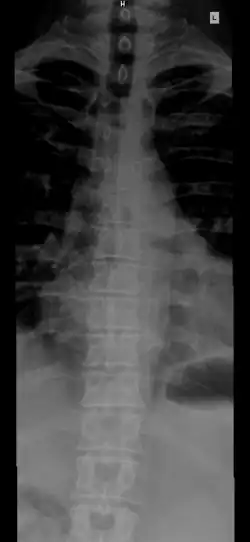

Позвоночник человека

«#» — шейный отдел (Pars cervicalis)

«#» — грудной отдел (Pars thoracalis)

«#» — поясничный отдел (Pars lumbalis)

«#» — крестец (Os sacrum)

«#» — копчик (Os coccygis)

Различают 5 отделов позвоночника:

- Шейный отдел (7 позвонков, C1—C7);

- Грудной отдел (12 позвонков, Th1—Th12);

- Поясничный отдел (5 позвонков, L1—L5);

- Крестцовый отдел (5 позвонков);

- Копчиковый отдел (3-4 позвонков)[2], иногда до 5).